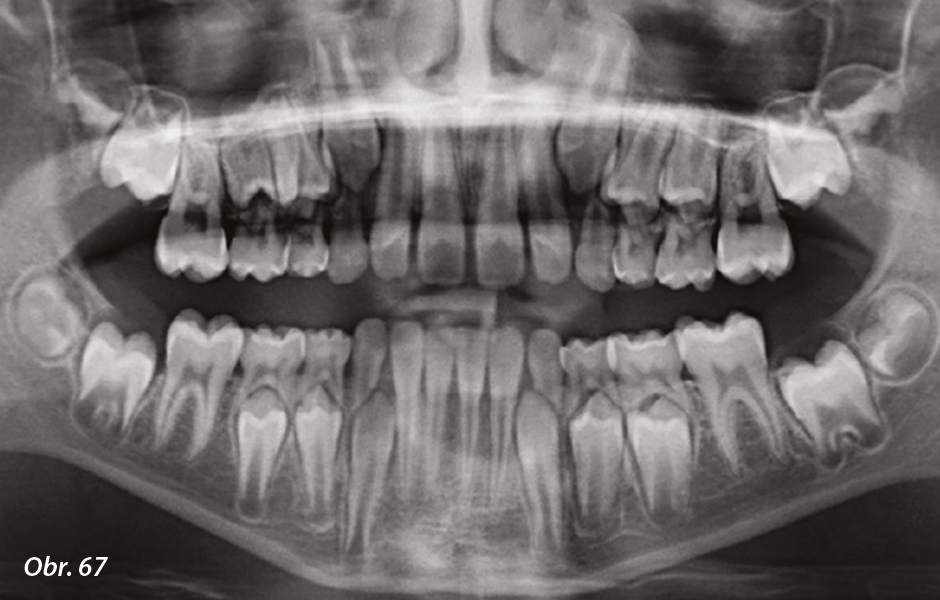

Obr. 66: Úvodní ortopantomogram: stěsnání horního zubního oblouku se zmenšením prostoru pro správné prořezání horních stálých řezáků.

Obr. 67: Ortopantomogram na konci terapie.

6letý pacient – závažná skeletální a dentální III. třída

Malokluze je charakterizována kolapsem horního zubního oblouku s obráceným skusem frontálně. Terapeutická sekvence zahrnovala následující kroky (obr. 58–67, viz fotogalerie):

- logopedická terapie

- elastodontická terapie pro III. třídu

- elastodontická retence po dobu asi 18 měsíců